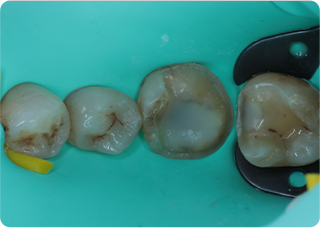

セラミックアンレー症例②

術前

むし歯除去&IDS

ラバーダム防湿

術後

| 主訴 | 右下奥歯の銀歯を白くしたい |

|---|---|

| 治療期間/回数 | 2週間、2回 |

| 価格(税込) | 143,000円(税込) |

| リスク・副作用 | セラミックの破損、一時的な知覚過敏が生じる場合がある |

| ポイント | 銀歯の中はむし歯になっていた。金属イオンにより歯の内部に黒い部分があるが、むし歯を染め出すう蝕検知液を使用し、選択的にむし歯のみを除去。また、セラミック装着時にラバーダム防湿を行うことで、詰め物の接着効果を最大限発揮できるようにした。 |